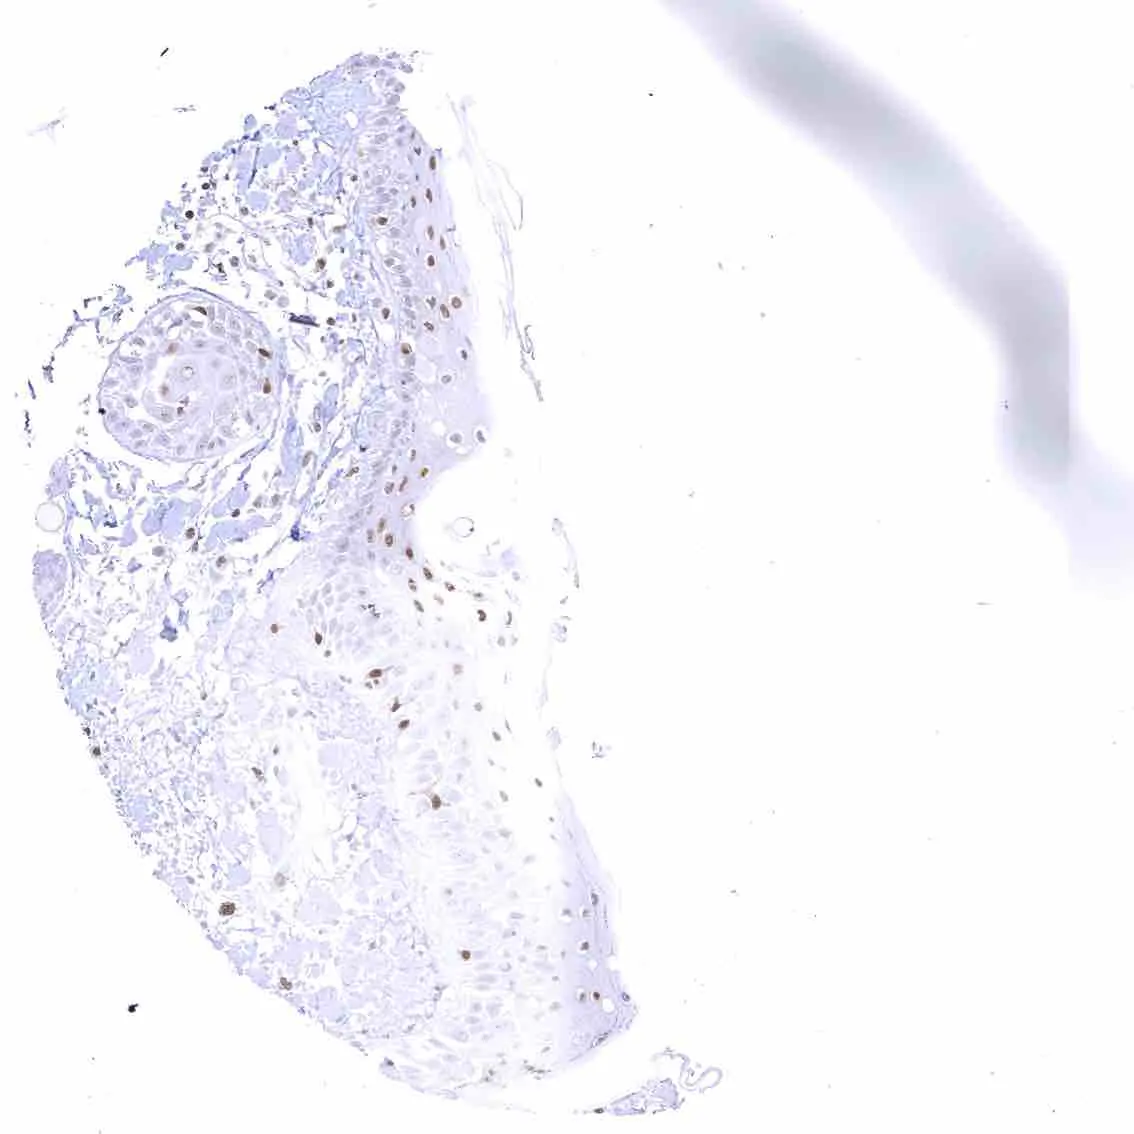

Tonsil – Strong nuclear p27 staining of a significant subset of cells, especially in the interfollicular area. Nuclear staining of squamous epithelial cells predominates in the more mature cell layers (top 50_ of the epidermis).

Tonsil, surface epithelium – Strong nuclear p27 staining of a significant subset of cells, especially in the interfollicular area. Nuclear staining of squamous epithelial cells predominates in the more mature cell layers (top 50_ of the epidermis).